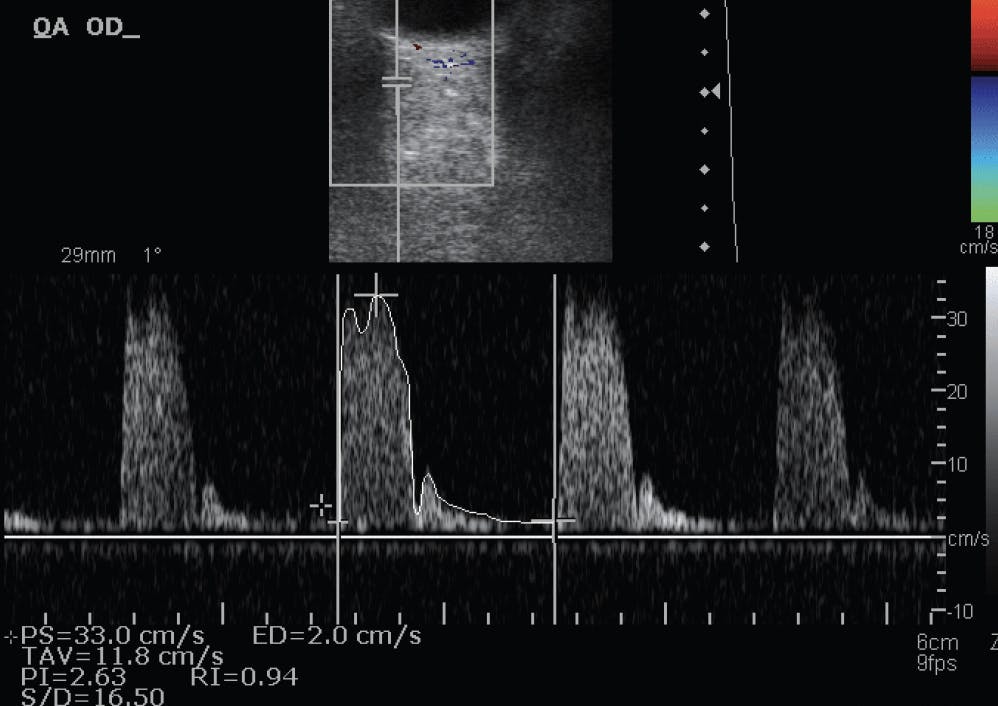

We found that patients with NTG had a higher resistive index (Figure) and lower early systolic acceleration in their retrobulbar vessels on CDI and a smaller arteriovenous retinal oxygen saturation difference on retinal oximetry. The global model (AUC 0.743) showed a significantly better discriminative ability than the conventional model (AUC 0.687, P = .049) or the advanced vascular model (AUC 0.677, P = .005). The conventional and advanced vascular models showed a similar discriminative ability (P = .0823).

<p>Figure. CDI of the ophthalmic artery of a patient with NTG in the Leuven Eye Study. There is a considerably high resistive index, which can be one of the many factors responsible for glaucomatous progression.</p>

Figure. CDI of the ophthalmic artery of a patient with NTG in the Leuven Eye Study. There is a considerably high resistive index, which can be one of the many factors responsible for glaucomatous progression.